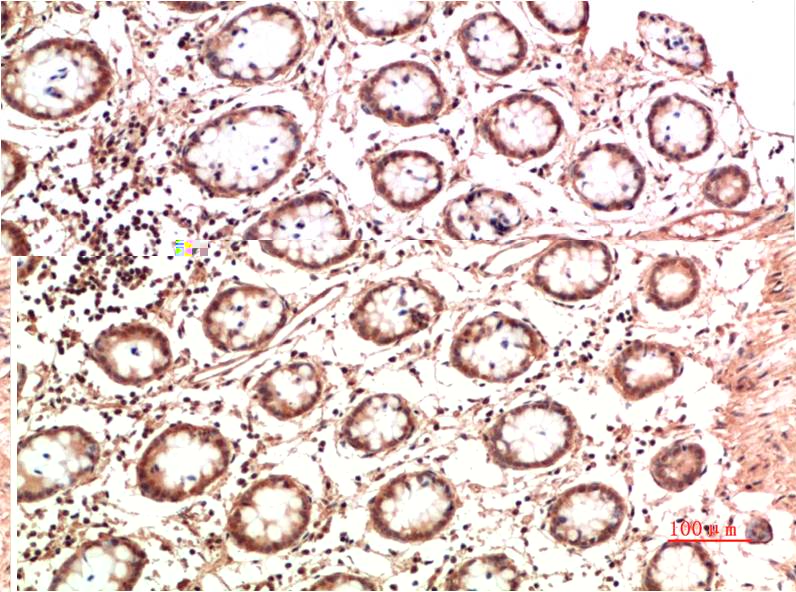

IkB α Rabbit Polyclonal Antibody

Applications :WB, IHC

| Recommended dilutions: | WB 1:500-2,000 IHC 1:50-300 |